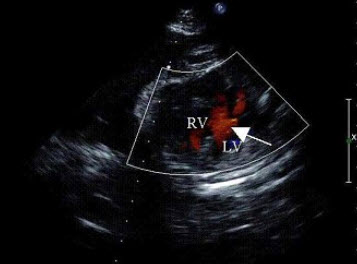

55、单项选择题

孕8周时感冒,产前超声检查胎儿心脏见图,最可能的诊断是()

A.单心室

B.房间隔缺损

C.室间隔缺损

D.大动脉转位

E.正常心脏